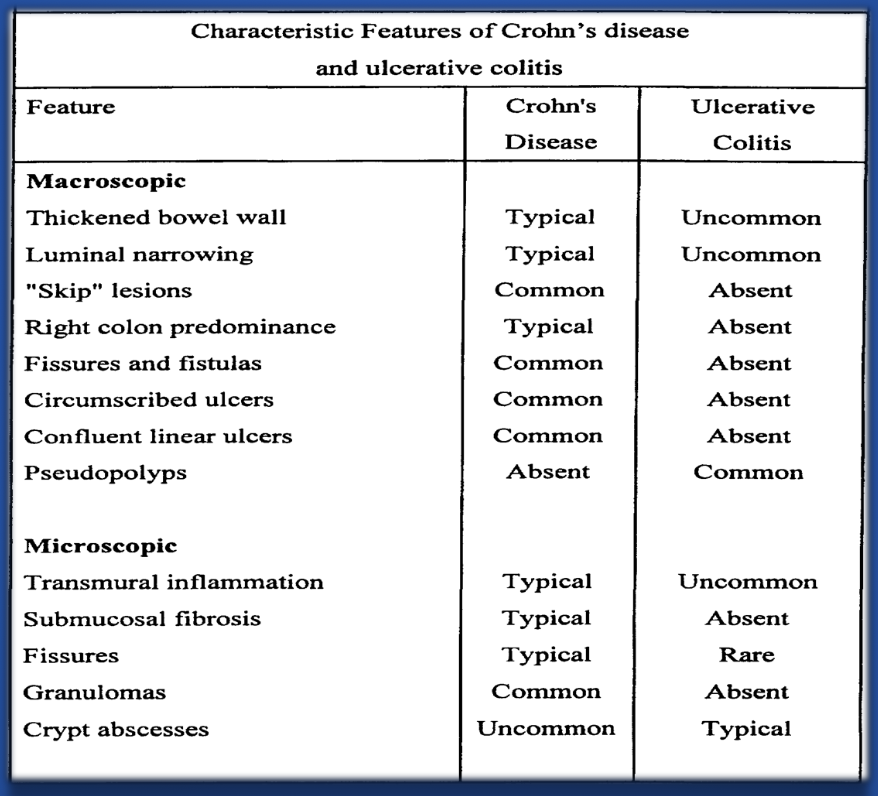

Comparison of Crohn’s Disease (CD) and Ulcerative Colitis (UC)

| Feature | Crohn’s Disease (CD) | Ulcerative Colitis (UC) |

|---|---|---|

| Location | Any part of the GI tract, mouth to anus, skip lesions | Colon and rectum only, continuous lesions |

| Depth | Transmural (all layers of bowel wall) may result in ulcers, transmural ulcers, resulting in fistula formation | Mucosa and submucosa only - rarely presents as feature of fistula formation |

| Inflammation | Patchy, granulomatous | Diffuse, continuous |

| Symptoms | Abdominal pain, diarrhea, weight loss, fatigue, fever | Bloody diarrhea, urgency, tenesmus, abdominal pain |

| Complications | Strictures, fistulas, abscesses, perianal disease | Toxic megacolon, perforation, colorectal cancer risk |

Table Comparision

| Feature | Ulcerative Colitis | Crohn Disease |

|---|---|---|

| Extent | Only colon involved | Panintestinal |

| Inflammation Pattern | Continuous, extending proximally from rectum | Skip-lesions with intervening normal mucosa |

| Depth of Inflammation | Mucosa and submucosa | Transmural |

| Perianal Lesions | Absent | Present |

| Granulomas | Absent | Noncaseating granulomas present |

| Bleeding | Common | Uncommon |

| Fistulae | Rare | Common |